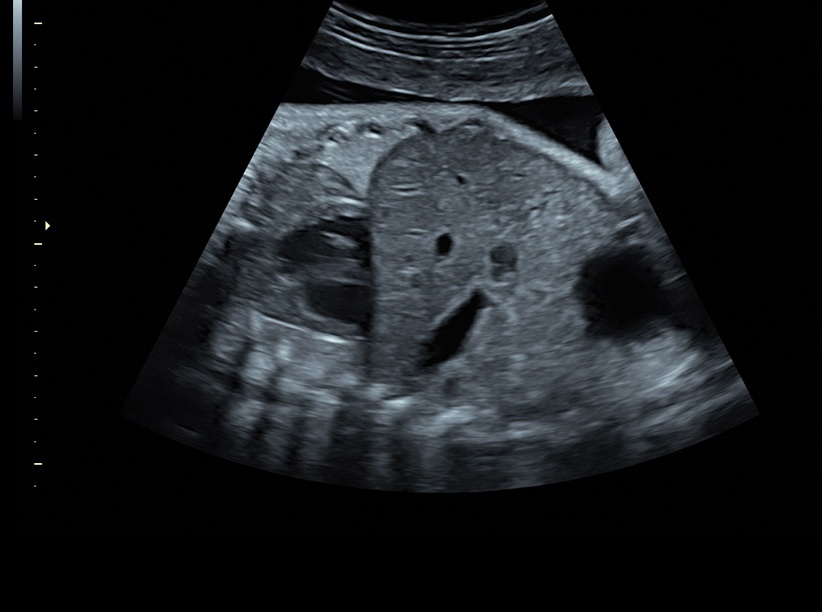

Ультразвуковая платформа Voluson S8 представляет собой оборудование экспертного класса с передовыми возможностями и высоким уровнем автоматизации процессов. Она позволяет проводить сканирование в режимах 2D, 3D и 4D с высоким качеством изображений.

Аппарат Voluson S8 базируется на надежной платформе VCA, которая имеет множество положительных отзывов. Она обладает высококонтрастной технологией объемной реконструкции, обеспечивая качественное воспроизведение изображений. Информация выводится на широкоформатный цветной монитор размером 23 дюйма для убедительной демонстрации плода будущим родителям и облегчения работы врача.

• Высокое качество изображений: Voluson S8 обеспечивает высококачественные изображения, позволяющие детально оценить состояние плода и обнаружить возможные патологии.

• Сложные инструменты для оценки качества плода: Сканер оснащен инновационными инструментами, позволяющими проводить детальную оценку состояния плода, включая его сердечную деятельность, анатомию и кровоток.

• Высокочувствительные датчики: Ультразвуковой сканер Voluson S8 оснащен высокочувствительными датчиками, что позволяет проводить полноценное обследование даже у пациентов с сложными анатомическими особенностями.